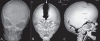

Harlequin appearance

Harlequin appearance of the orbit represents the elevation of the superolateral angle of the orbit along with a flat frontal bone on a plain radiograph [Figure 19A–C].[23] It is seen in coronal craniosynostosis, where the anteroposterior growth of the skull is limited. There is also relative increase in the transverse diameter of the skull, which is called brachycephaly. The orbit is shallow, the lesser wing of the sphenoid is elevated, and the greater wing is expanded. The innominate line (superior border of the greater wing of the sphenoid) appears as a dense ridge. The sign can be unilateral or bilateral.

fig ft0fig mode=article f1

Figure 19 (A–C)

caption a4

Harlequin appearance. Frontal view of the skull (A) in a child with Apert syndrome shows elevated superolateral angles of both orbits giving the appearance of a ‘harlequin mask.’ Frontal (B) and lateral (C) surface-shaded display 3D CT …